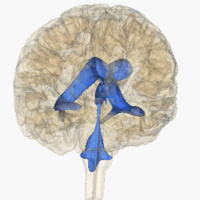

![]() Rotating 3D rendering of the four ventricles and connections. From top to bottom: Blue - Lateral ventricles Cyan - Interventricular foramina (Monro) Yellow - Third ventricle Red - Cerebral aqueduct (Sylvius) Purple - fourth ventricle Green - continuous with the central canal (Apertures to subarachnoid space are not visible) | |